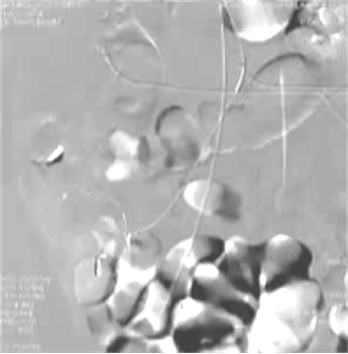

(1)操作流程·诊断性血管造影:用5F导管插管至肠系膜上/下动脉,寻找造影剂外溢(活动性出血)直接或间接征象 · · 超选择插管:通过同轴技术引入3F微导管,尽可能将导管送至直动脉(vasa recta) 或出血点最远端 · · 栓塞:首选微弹簧圈(2-3mm × 20-30mm),放置2-3个即可;也可用聚乙烯醇颗粒(>250μm);禁用液体栓塞剂(如酒精),因其肠坏死率高 · · 终点:造影证实外溢停止,同时保留近端和远端血流(不牺牲侧支循环) · (2)栓塞程度:多少算够?多少算多?理想情况:仅栓塞出血点所在的直动脉 若无法超选至直动脉,可栓塞边缘动脉(marginal artery),但必须确保:

o 栓塞长度控制在3-4 cm以内(作者经验),避免过大范围缺血 o 栓塞的目标不是完全阻断血流,而是降低出血点的灌注压,配合局部血管痉挛和患者自身凝血能力形成血栓 5. 微导管远端栓塞临床数据:疗效与安全性一篇发表在2004年的文章汇总了12项研究【Brian Funaki 2004】、超过150例病例,核心数据如下:

8. 微导管远端栓塞临床意义总结这篇文献的价值在于:1. 提供了历史背景:解释了为什么栓塞技术从“弃用”到“复兴”的关键转折点是微导管技术 2. 给出了扎实的数据:多篇研究证实成功率>80%、肠梗死率接近0% 3. 明确了技术细节:栓塞到什么程度、用什么材料、哪些情况要谨慎(如右结肠/盲肠出血) 4. 确立了地位:微导管栓塞是内镜失败或不适用时,处理严重下消化道出血的首选血管内治疗 为什么远端栓塞?下消化道出血栓塞共轴导管选择使导管到达终末支的位置更满意